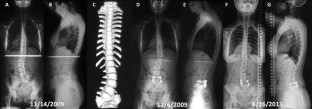

One-stage posterior-only lumbosacral hemivertebra resection with short segmental fusion: a more than 2-year follow-up

This retrospective study of a prospective collected database comprises a consecutive series of 14 congenital scoliosis due to lumbosacral hemivertebra treated by 1-stage posterior hemivertebra resection with short segmental fusion, with at least a 2-year follow-up period (24–144 months). Surgical reports and patient charts were reviewed. Radiographic evaluation included measured changes in segmental scoliosis and lordosis, compensatory scoliosis, thoracic kyphosis, lumbar lordosis, and trunk shift. Quality of life data from Scoliosis Research Society (SRS)-22 questionnaires were also collected.

Our results showed that the mean follow-up period was 38.4 months. The mean fusion level was 3.2 segments. Mean operation time was 207.8 min with the average blood loss of 235.7 ml. The mean segmental scoliosis was 30° preoperatively, 5° postoperatively (83 % correction rate), and 4° (87 %) at the latest follow-up. The compensatory coronal curve of 30° was spontaneously corrected to 13° at most recent follow-up. Trunk shift was significantly improved on both coronal (63 %) and sagittal plane (58 %) after the surgery, and kept stable during the follow-up. The total SRS-22 score, the self-image domain score and the satisfaction domain score demonstrated significant improvement compared with preoperative status. Only one intra-operative complication was observed, a pedicle fracture.

In summary, our results showed that one-stage HV resection and short segment fusion by a posterior approach can offer excellent scoliosis correction and trunk shift improvement without neurological complications, while saving motion segments as much as possible. This strategy is not only corrective of the deformity but also preventive of compensatory curve progression, thus avoiding long lumbar fusion.